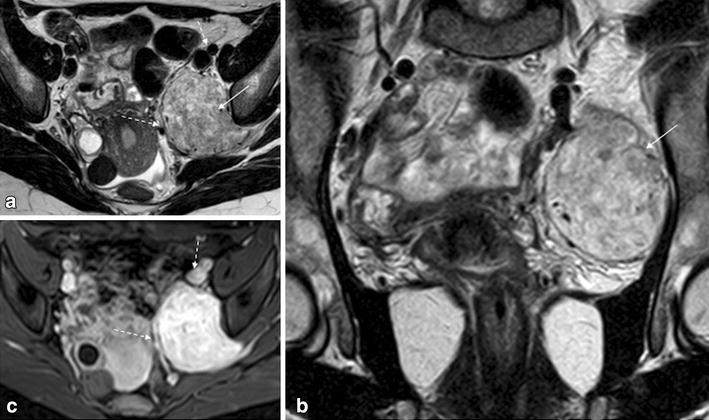

Explore over 6700 anatomic structures and more than 670 000 translated medical labels. Magnetic resonance mr imaging is a valuable technique for the non invasive evaluation of the female pelvic region for example diagnosing or staging developmental anomalies leiomyomas adenomyosis vaginal neoplasms endometrial or cervical carcinoma. Click on a link to get t1 axial view t1 coronal view.

Use the mouse scroll wheel to move the images up and down alternatively use the tiny arrows on both side of the image to move the images on both side of the image to move the images. This mri female pelvis axial cross sectional anatomy title tool is absolutely free to use. Mri of the female pelvis 1 mri of the female pelvis normal anatomy 2 mri of the female pelvis adenomyosis adenomyosis normal f 52 years f 17 years 3 mri of the female pelvis adenomyosis adenomyosis normal f 52 years f 17 years 4 mri of the female pelvis adenomyosis f 33 years 5 mri of the female pelvis adenomyosis f 41 years 6 mri of the.